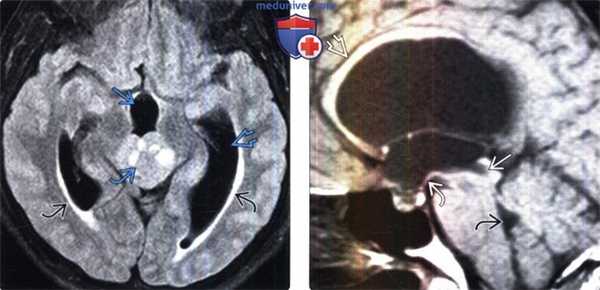

Коллоидная киста – это врождённое нейроэпителиальное образование. Коллоидная киста выстлана эпителием и имеет фиброзную капсулу. Она составляют около 1-2% объемных внутричерепных образований. Обычно диагностируются в возрасте между 30 и 50 годами. При МРТ головного мозга видно, что киста всегда расположена в переднее-верхнем отрезке III желудочка между отверстиями Монро. Контур ее четкий, форма округлая, содержимое бывает неоднородное. Размер от 3 мм до 4 см, при больших размерах она закрывает отверстия Монро и вызывает окклюзионную гидроцефалию. Сигнал зависти от примеси белка к ликвору. При наличии белкового мукоидного содержимого киста гиперинтенсивна на Т1-взвешенных МРТ и гипоинтенсивна на Т2-взвешенных МРТ, но встречаются варианты гиперинтенсивные на томограммах обоих типов кольцевидные или смешанные . Контрастирования не наблюдается.

КТ и МРТ головного мозга. Коллоидная киста III желудочка.